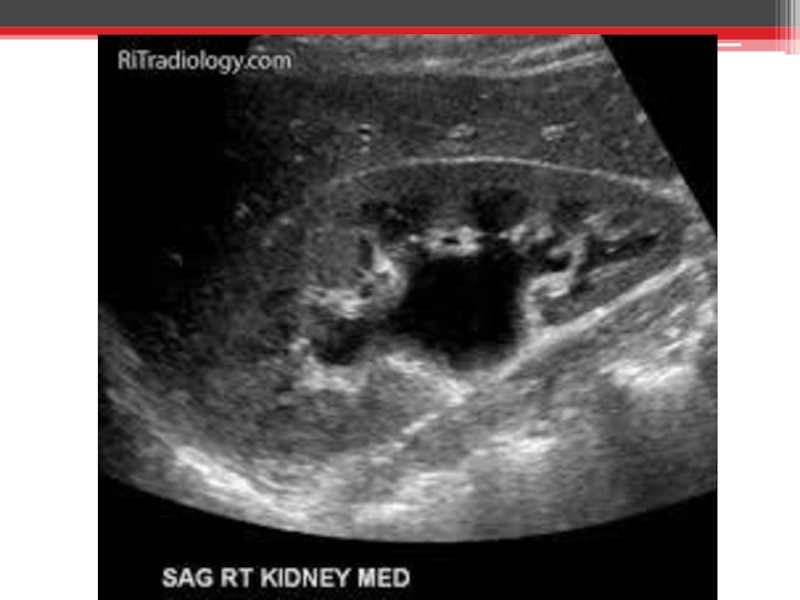

Атрезія дівочої пліви. Гематокольпос. Гематометра. Гематосальпінкс. Гострий місцевий перитоніт. Гостра затримка

сечі. Гідрокалікоз.